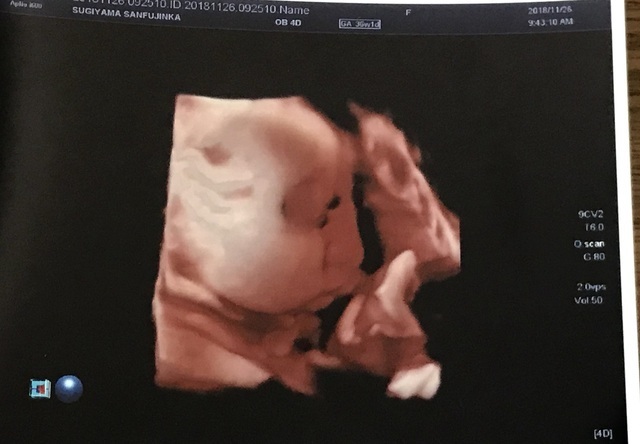

36週2日(36w2d・男の子)|kikilala さん(31歳)

エコー写真撮影時のエピソード:

なかなかお股を見せてくれず性別が間際までわかりませんでした。顔はよく見せてくれて、エコーの写真はこっちを向いています。

しかし、4Dエコーを撮るときだけは手で顔を隠していました(笑)恥ずかしがり屋さんなのかな?と病院の方と話しました。

やっと見せてくれた顔が私にそっくりで、うまれてきた顔も私にそっくりな息子です。